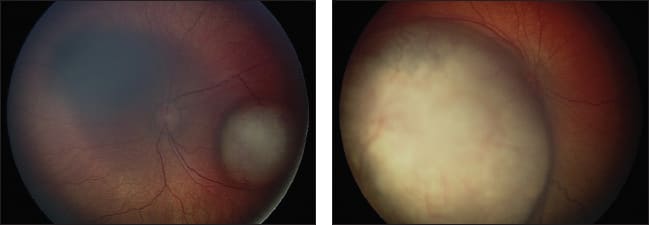

Figure 3. Superselective ophthalmic artery cannulation, followed by an angiogram showing vascular supply to the eye and focal delivery of chemotherapy.

Further consideration is also needed pertaining to the vasculature in patients previously treated with systemic or local chemotherapy, as well as radiation. BPEI has reported on the vascular alterations of these treatment modalities, which may potentially decrease the delivery of chemotherapeutics during intra-arterial infusion.14